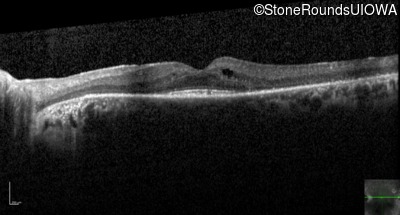

Optical Coherence Tomography - Right - 20/32

Exemplar / OCT Stack

Optical Coherence Tomography - Left - 20/32